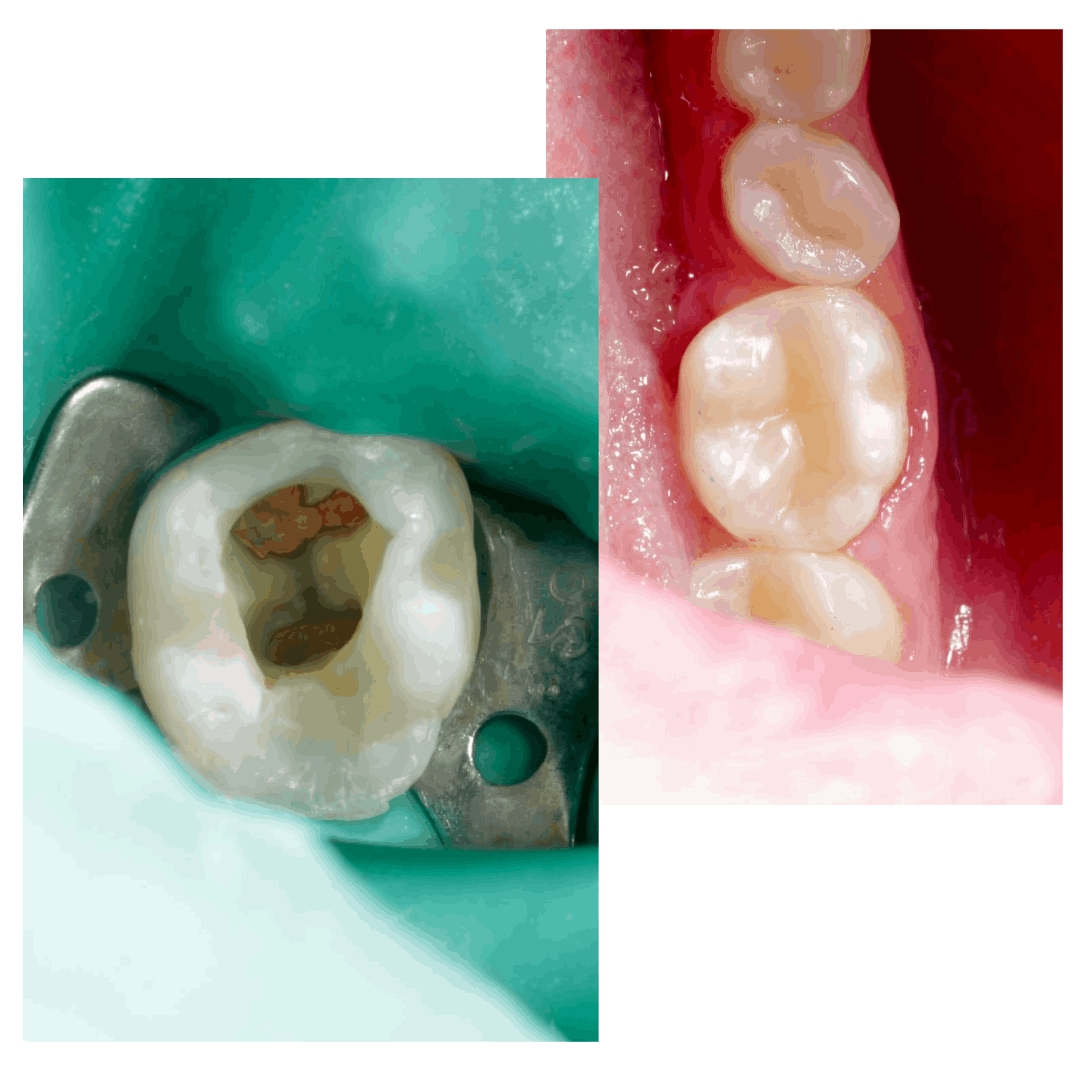

Попытки самостоятельно достать фрагмент привели к перерасширению.

Два визита: первый извлечение, второй завершение работы.